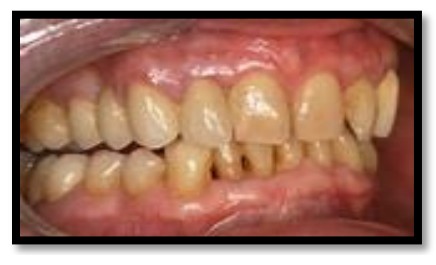

-Un diabète est suspecté devant des antécédents familiaux de diabète, des signes généraux et des signes oraux (gingivites persistantes, parodontites sévères, candidoses, aphtes, poly caries, sécheresse buccale, retards de cicatrisation,